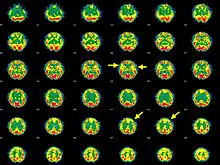

- Single photon emission computed tomography هیپوپرفوزیون متمرکز و کانونی را نشان میدهد(۷۵٪ موارد)